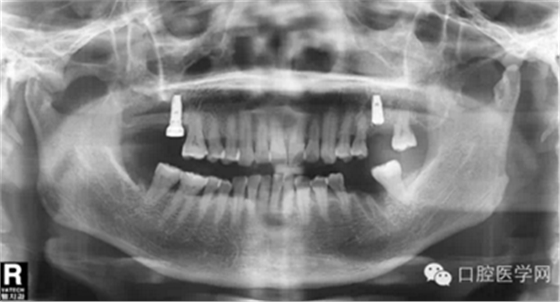

那么今天我给大家展示临床上比较常见的几种品牌的种植体的X光片,网友们可以通过X光片来仔细查看不同种植体之间的区别。因为本人能力有限,不能每一样种植体都拿来尝试使用,所以我目前收集到的种植体的X光片数量有限,但是本人日后还会不断的去寻找不同品牌种植的资料,然后补充道这篇文章中,以供大家参考。

需要特殊声明的是:以下所有的照片中有本人自己的病例术后X光片,也有本人在网络上搜集到的X光片(并非本人的临床病例),所以在此暂不讨论种植体手术植入的角度和设计方案等问题,本文的主要目的是像广大读者展示不同品牌种植体在植入颌骨内拍摄X光片后所显示的形状,用以区别不同品牌的种植体。

第五种,瑞士士卓曼种植体(也称ITI种植体)

第六种,美国3I种植体

第七种 韩国美格真种植体